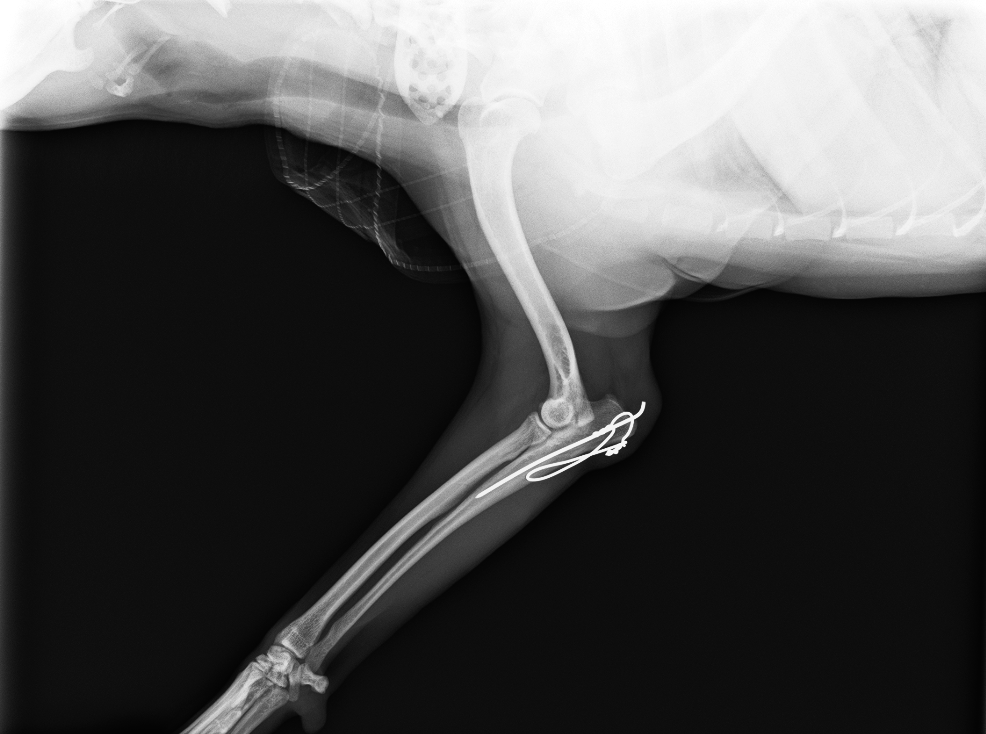

髄内ピン、テンションバンドワイヤーによる固定

after